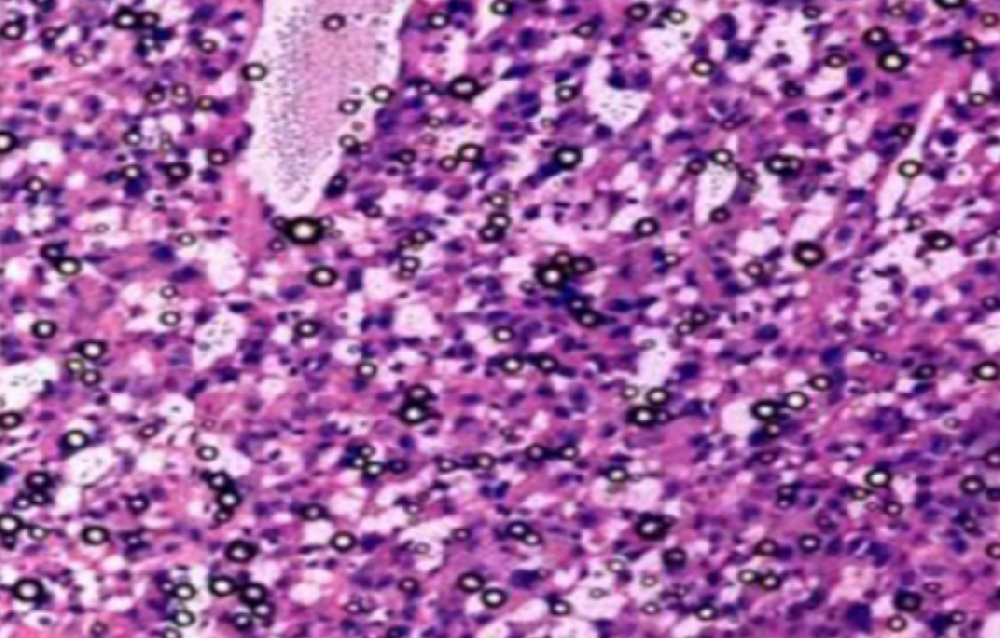

HE染色,全称苏木精-伊红染色法(Hematoxylin and Eosin staining),是最常见的组织切片染色技术之一,用于在显微镜下观察和分析组织或细胞的结构和形态。

虽然HE染色是最常见且最基础的染色技术之一,😭但在实验过程中,很容易出现各种情况导致染色切片质量参差不齐。所以,小编根据以往实验经验,给大家整理归纳出了15个HE染色中的常见问题,还包含问题原因分析以及解决方法哦~